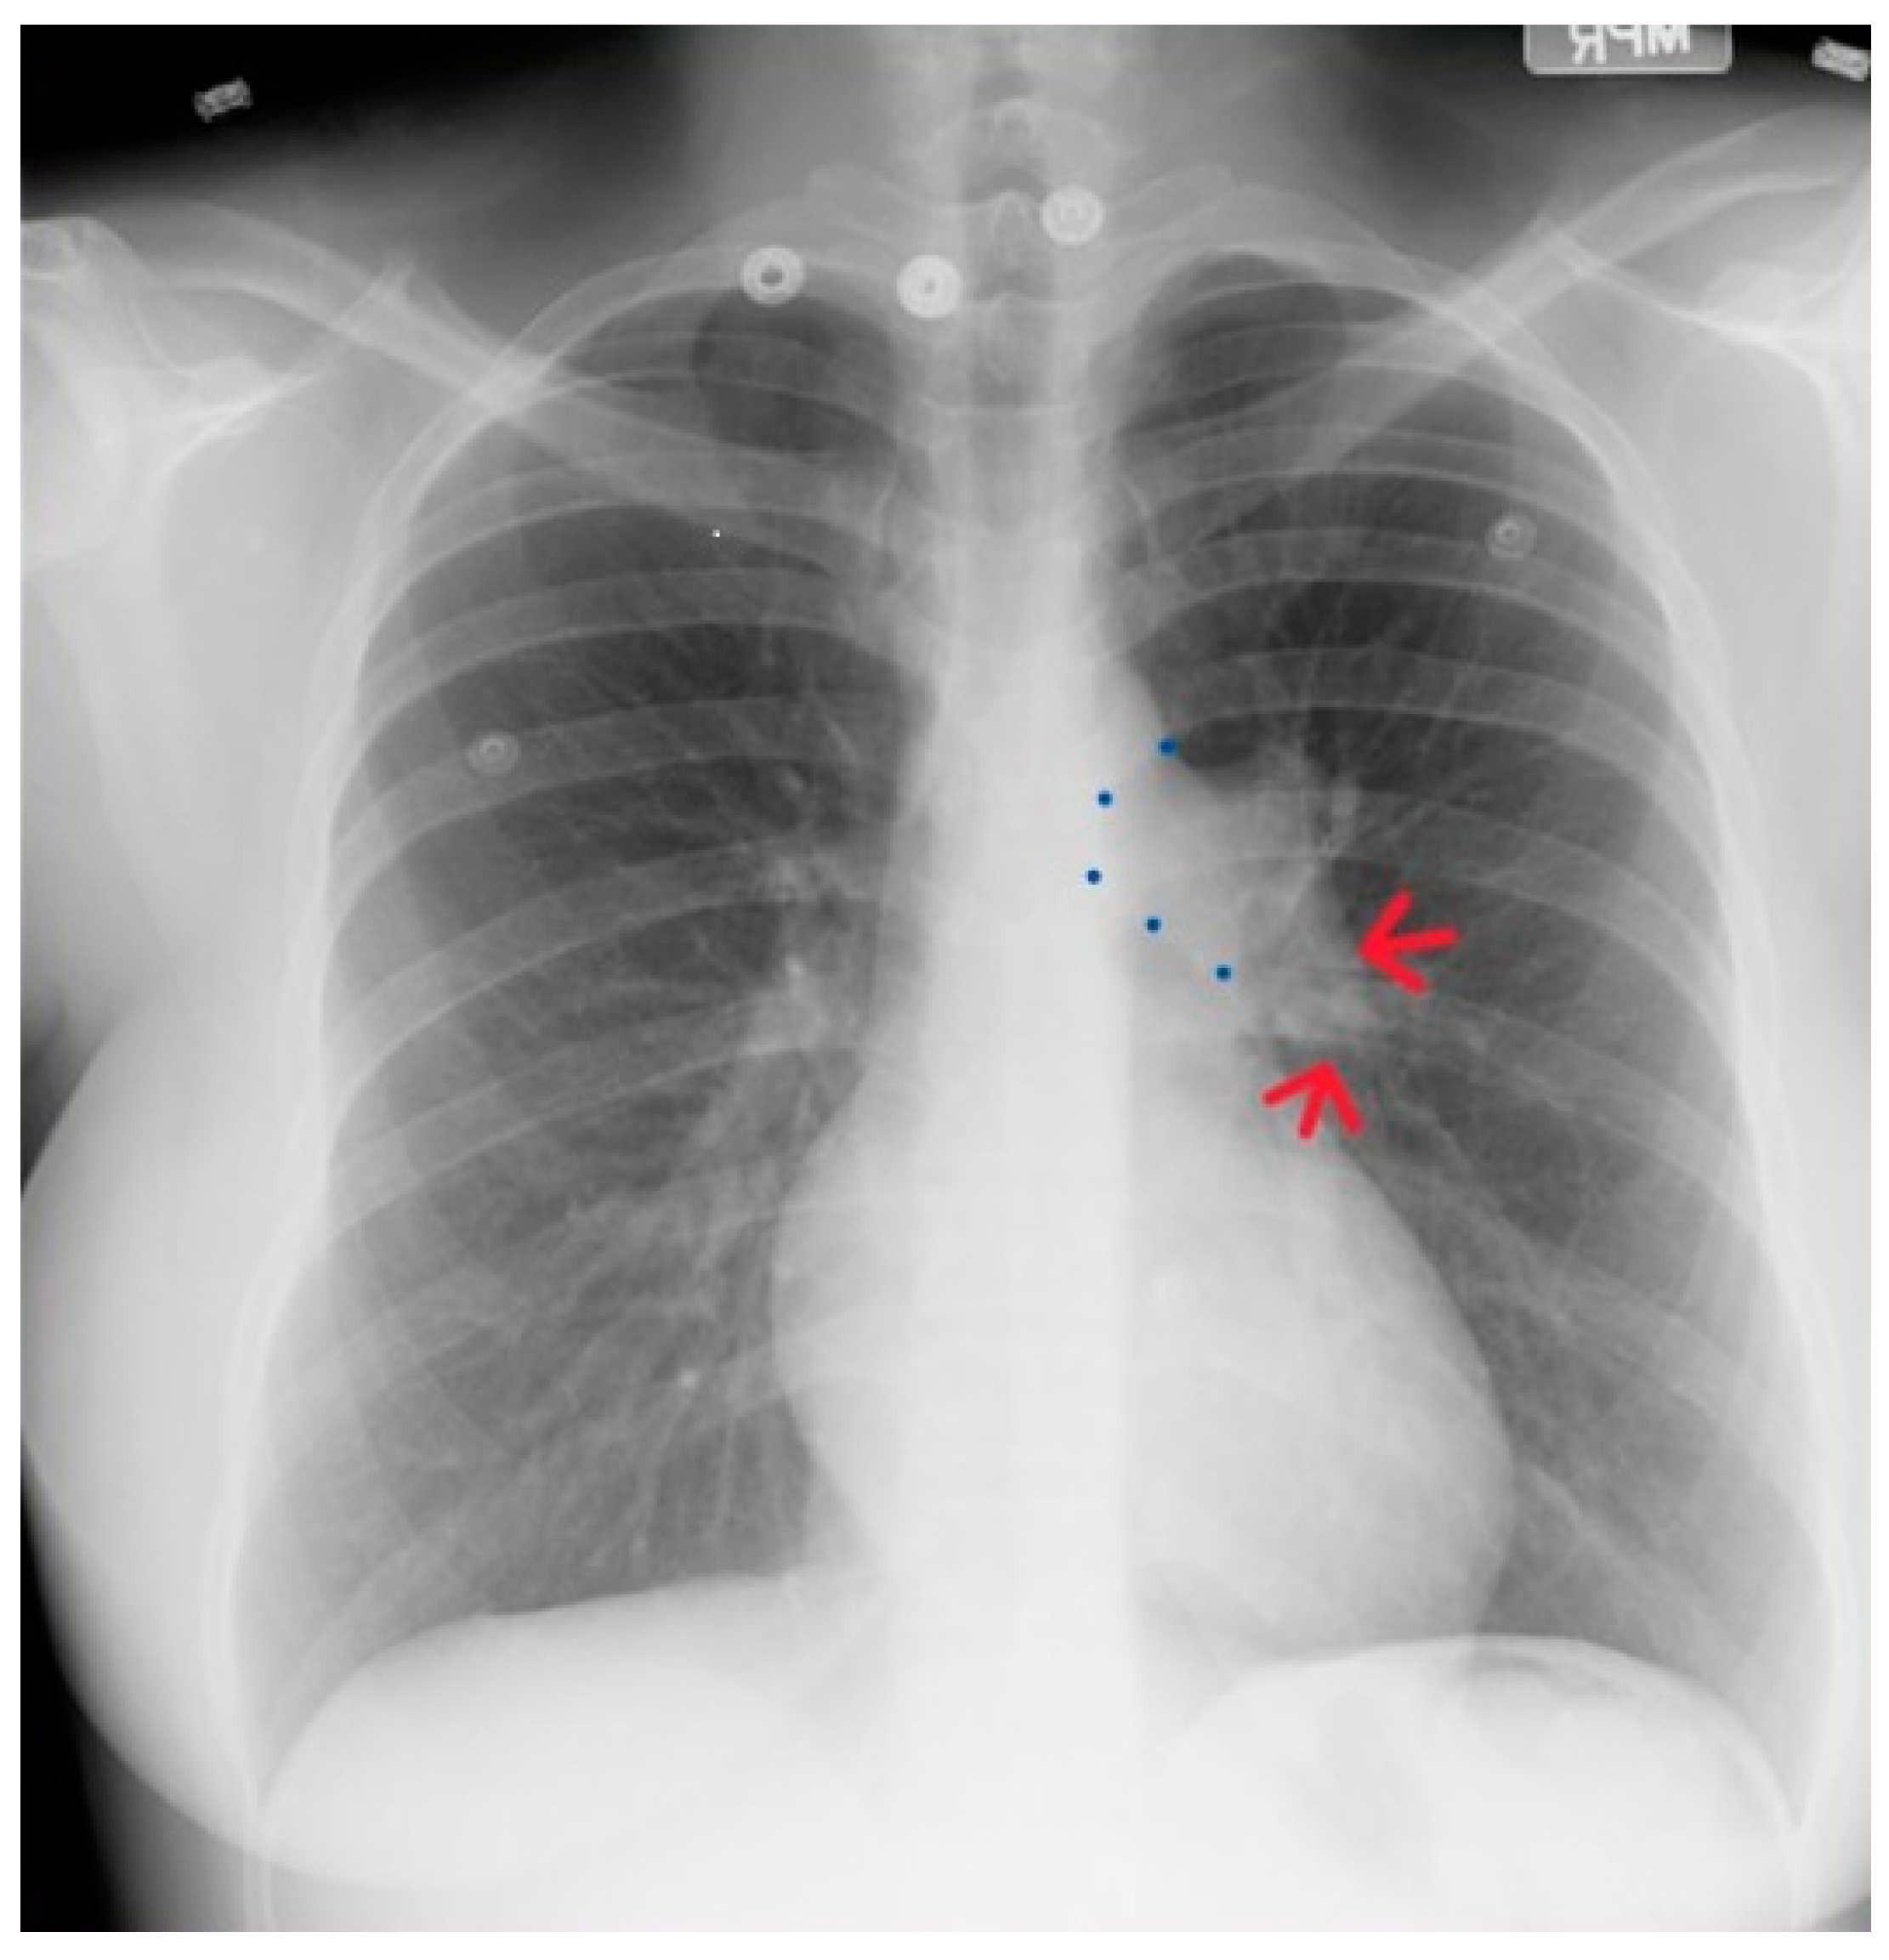

Figure 19.

Posteroanterior chest X-ray of severe pulmonary stenosis: this chest X-ray is of a 31-year-old female who presented with worsening exertional dyspnea over the last two years. Her exam revealed elevated jugular venous pressure with prominent A wave. She was noted to have a right ventricular lift with a grade 4/6 systolic ejection murmur best heard at the left upper sternal border. The chest X-ray is well centered and there is a good inspiration. The cardiothoracic ratio is normal. The pulmonary trunk is enlarged (its right border is outlined by blue dots as it passes over the left bronchus). The left pulmonary artery branch that is indicated by two red arrows is also enlarged. Her echocardiogram revealed severe pulmonary valve stenosis with peak gradient 68 mmHg and mild pulmonary valve regurgitation. She subsequently underwent balloon valvuloplasty with reduction of her peak gradient to 24 mmHg. Her symptoms of dyspnea had resolved a few months post-procedure.